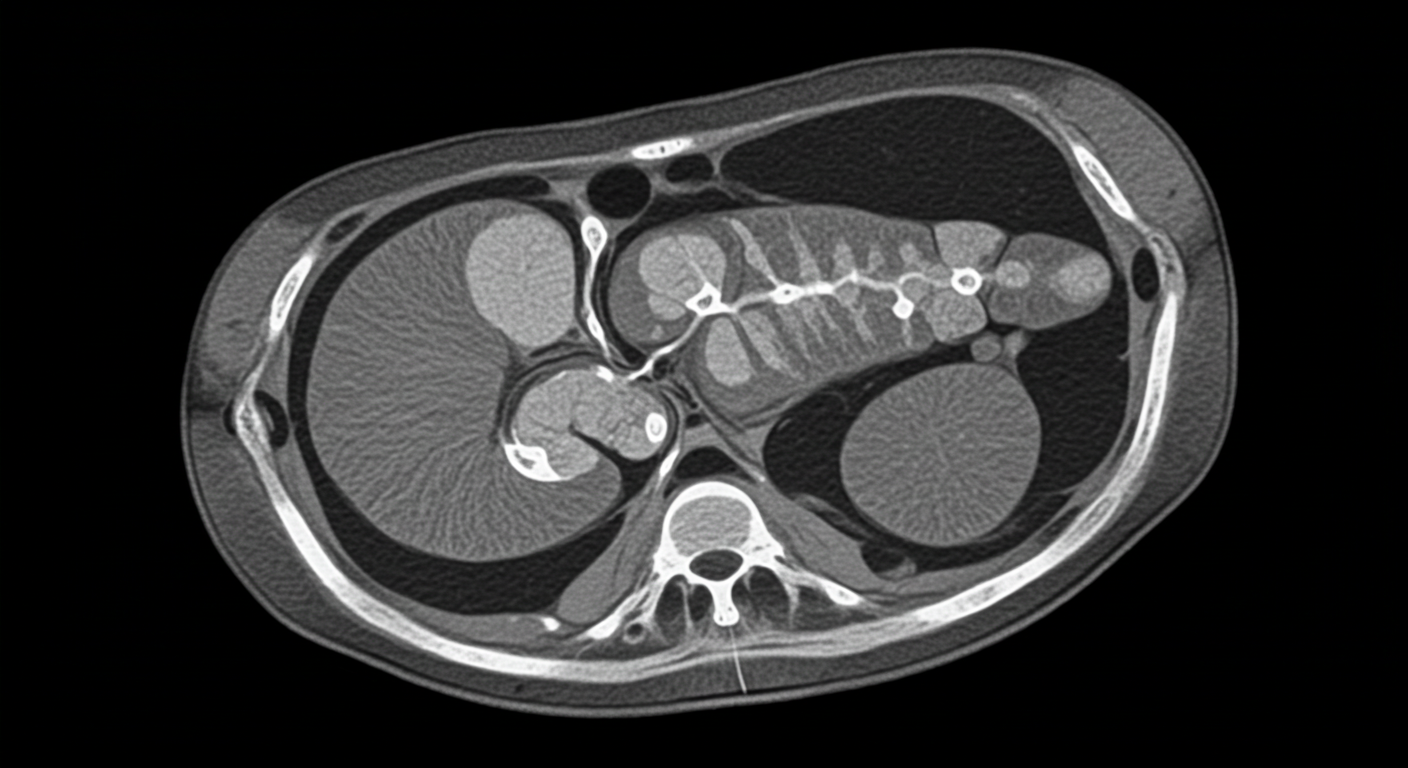

3. 췌장 낭종

췌장 안에 물혹(낭종)이 생기는 질환으로, 대부분 양성이며 우연히 발견됩니다. 하지만 일부 낭종은 암으로 발전할 수 있어 정기적인 추적관찰이 필요합니다.

⚠️ 구분 포인트

통증보다는 정기검진에서 우연히 발견되는 경우가 많으며, 낭종 크기 변화나 증상이 나타나면 정밀 검사가 필요합니다.